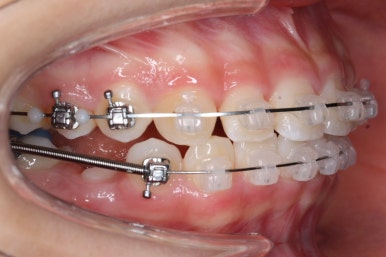

아래쪽이 더 시급하므로 브라켓 부착을 하여 가지런히 하기 시작했고 위쪽은 악궁확장장치를 입천장에 하여 위턱뼈를 가로로 넓혀주기 시작합니다.

악궁확장장치는 총 4-6개월 정도 부착하고 있으며 그 이후에는 입안에서 제거하게 됩니다.

윗니에도 이제 장치를 모두 붙였습니다. 아래쪽은 어느 정도 가지런해지고 나면 부족한 자리를 만들어주기 시작합니다.

예상한대로 자리만 충분히 마련해주니 그동안 나오지 못하고 막혀있던 치아가 슬그머니 고개를 내밀고 있습니다.

좀 더 기다렸다가 좀 더 올라오면 장치를 부착해서 정리해주기만 하면 되겠습니다.

부산치아교정잘하는곳 키다리아저씨치과에서는 치아가 올라오자마자 장치를 부착하여 가지런하게 해줍니다. 이제 어느 정도 큰 그림은 그려졌다고 보시면 되겠습니다.